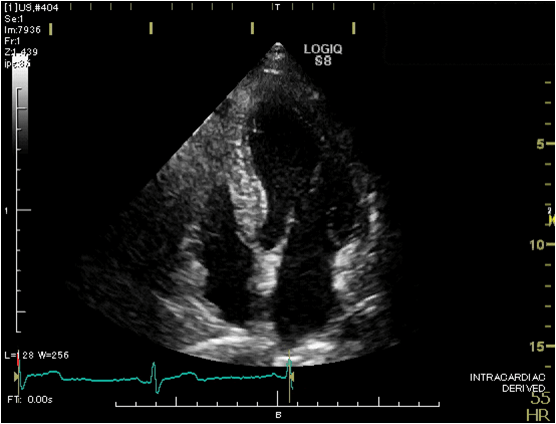

心臓超音波検査

(心エコー検査)

心臓の形や動き、弁の状態、血液の流れなどを調べる検査です。

ベッドに左向きで横になっていただき、胸にゼリーを塗り心臓を観察します。

必要に応じて仰向けや右向きになったり息を止めたりして撮影します。

検査時間は通常20~30分程度です。

超音波診断装置(心臓用)

心臓の超音波画像